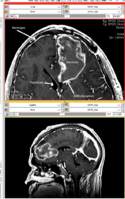

• inner part of the tumor segmented from SPGR

• outer part of the tumor segmented from post-Gad

• WM and GM segmented from N4-processed SPGR (WM segmentation of the original SPGR volume is included, note under-segmented WM in the skull base)

• all segmentations were done using FastMarching, fiducials are included for each of the segmentations

• no fine-tuning of the fiducial locations was done -- this is an example result one can get almost right away

• rule of thumb in placing fiducials: try to cover uniformly the volume you are trying to segment; this is particularly important for large structures like WM/GM